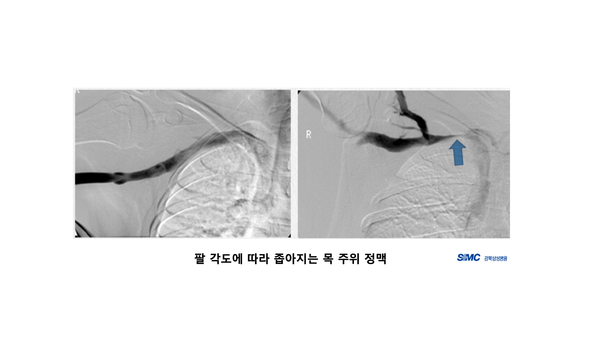

하지만 TOS는 일시적으로 나타났다가 호전되는 경우도 많기 때문에, 신체검진으로도 불확실할 수 있다. 그렇기 때문에 메디컬 팀, 트레이너, 선수 간의 지속적인 대화를 통해 매일 매일의 증상 변화 및 양상을 꾸준히 추적하는 것이 가장 중요하며 의심이 된다면 혈관조영술, MRI 등으로 해당 부위를 확인해야 한다.